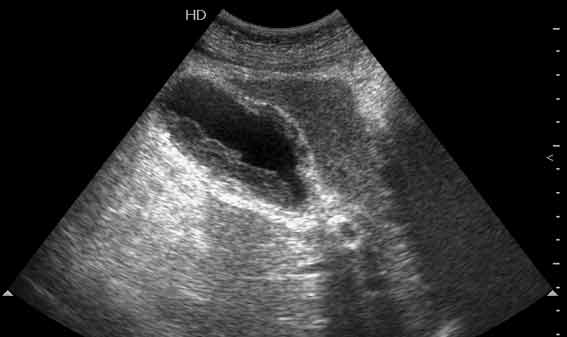

Пожилой мужчина, камни в желчном пузыре не обнаружены.

Наиболее частая причина некроза стенки ж.пузыря у пожилых людей без признаков ЖКБ - атеросклеротическое поражение и тромбоз пузырной артерии.

На сонограмме определяется очаг некроза передней стенки ж.пузыря - потеря характерной слоистости утолщенной стенки, характерной для флегмонозного воспаления, на некотором ее участке.